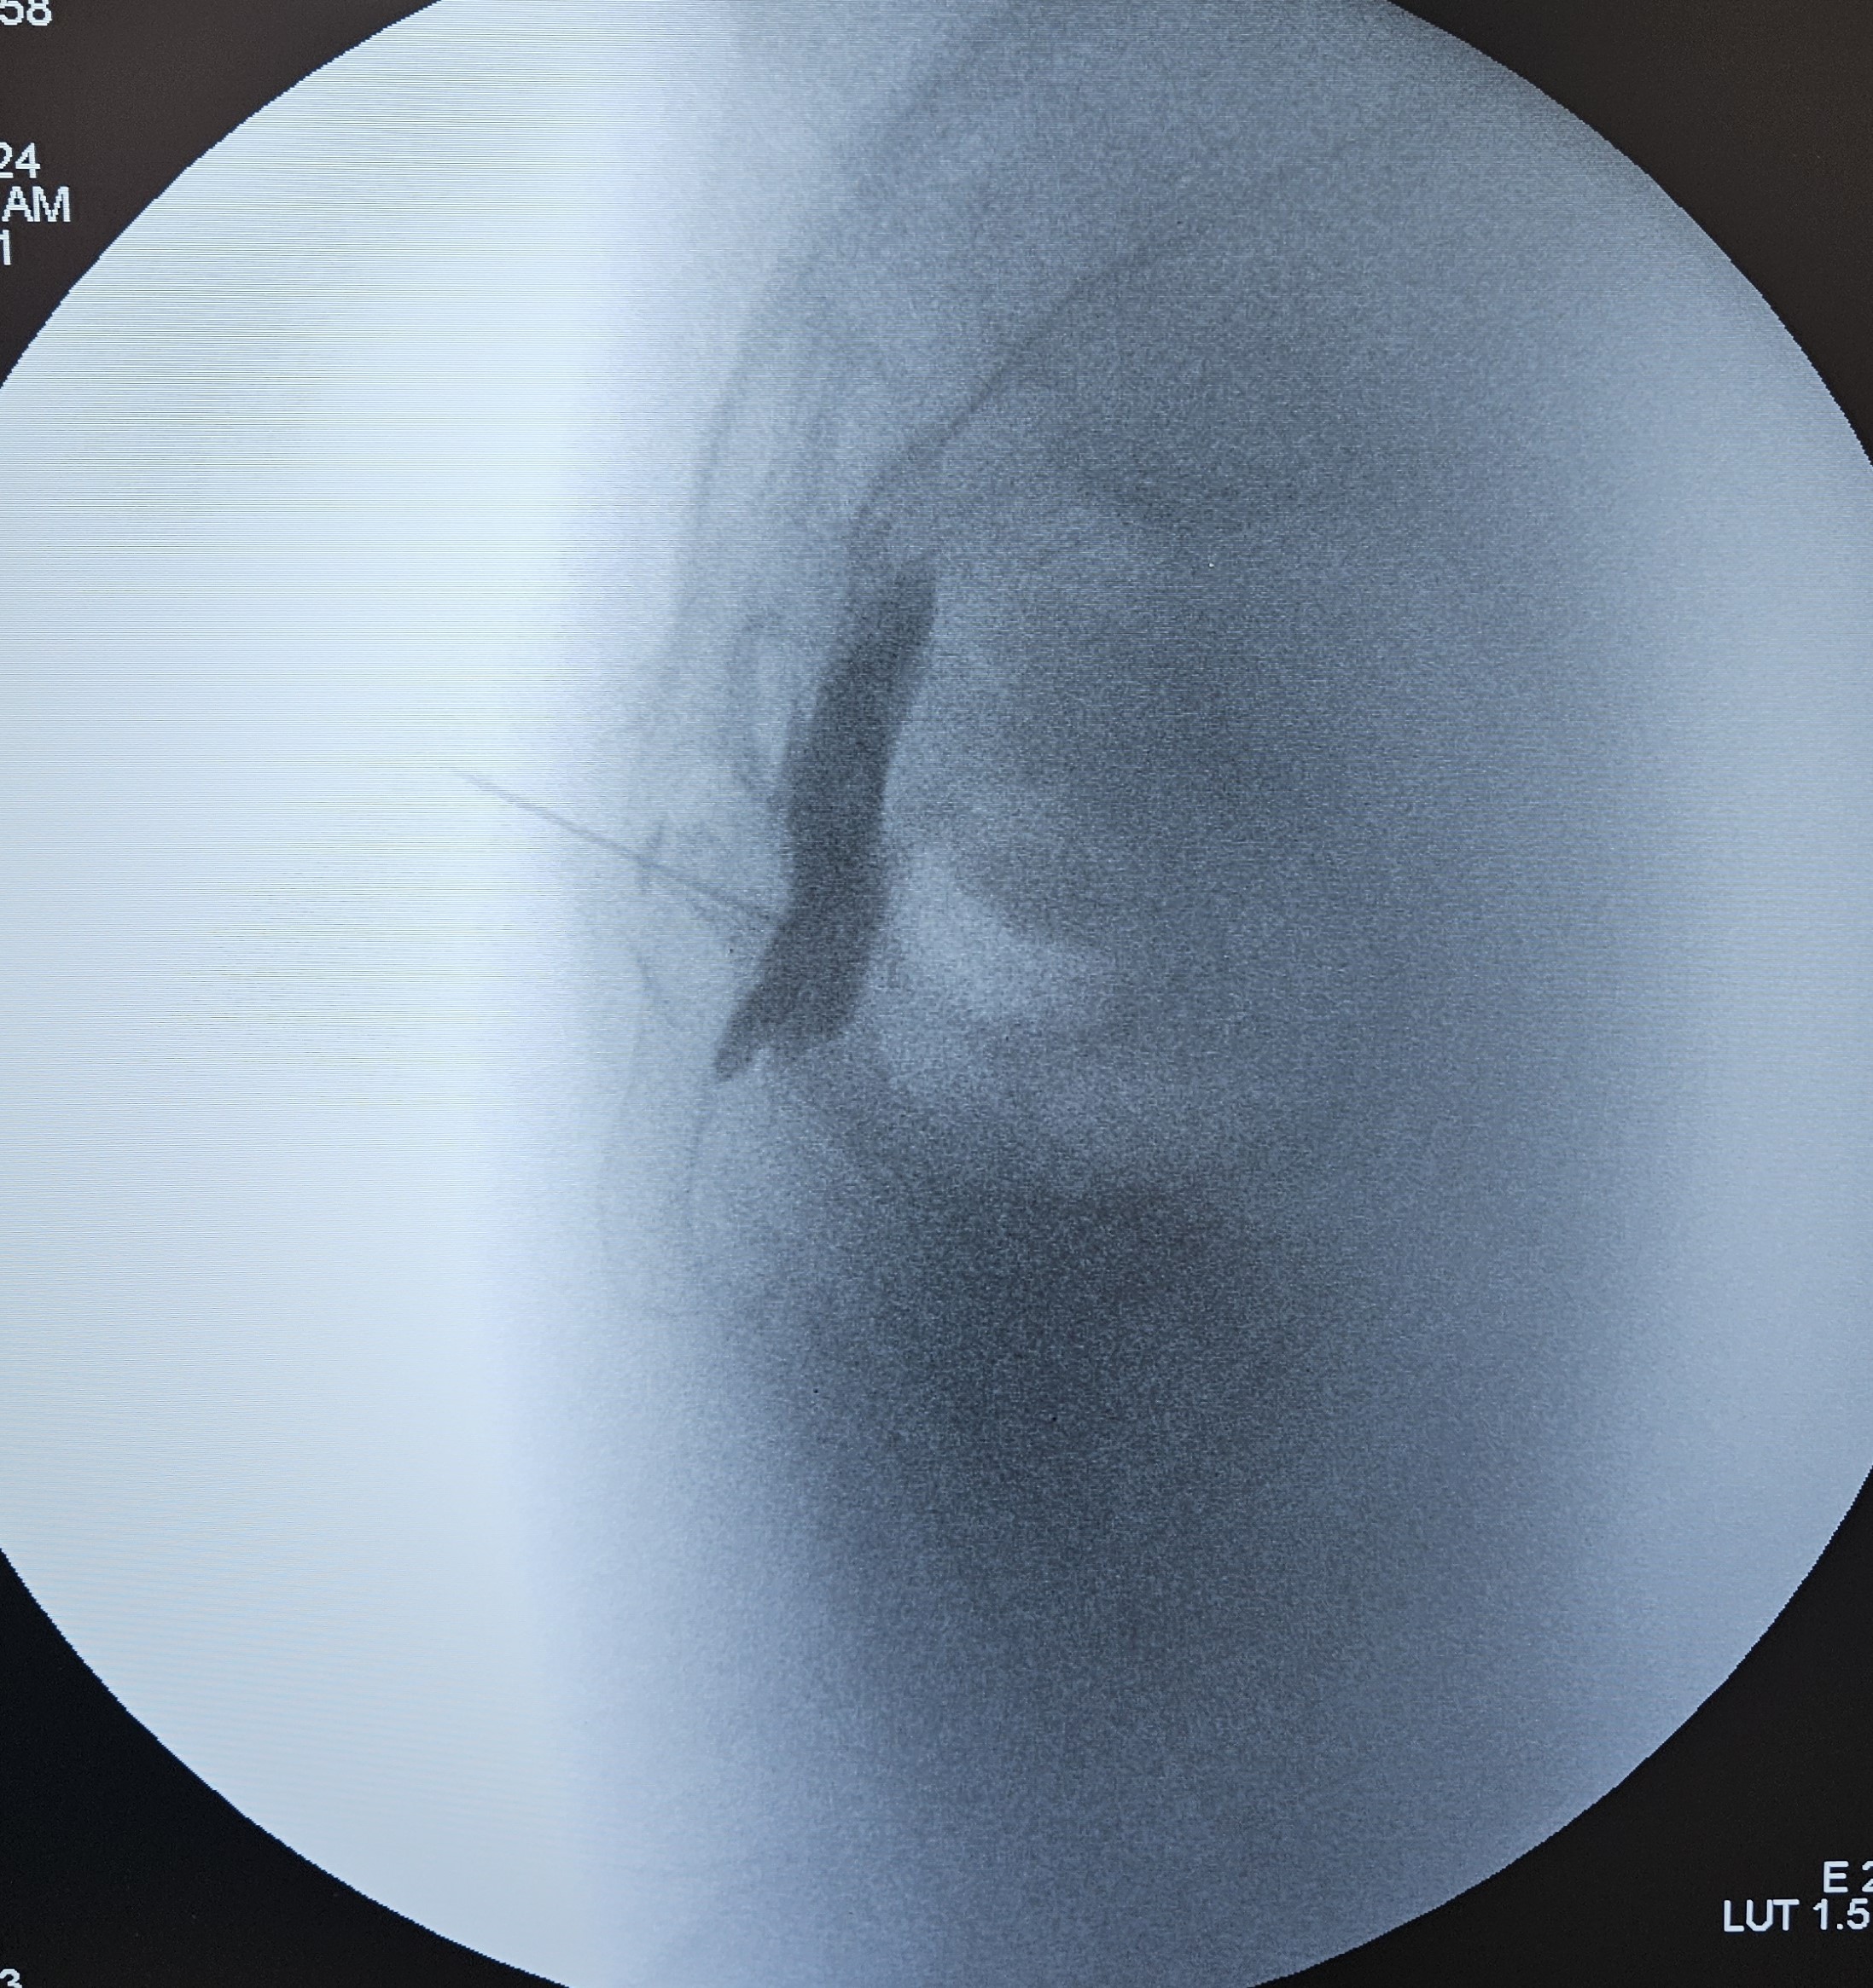

Με τον ασθενή σε πρηνή θέση και υπό τοπική αναισθησία και ακτινοσκοπική καθοδήγηση, εισάγεται μια λεπτή βελόνα, η οποία διαπερνά τον ιεροκοκκυγικό σύνδεσμο και μέσω άρθρωσης προωθείται ακριβώς κάτω από τον κόκκυγα, όπου βρίσκεται το γάγγλιο. Ακριβώς μπροστά από το γάγγλιο εδράζεται το ορθό, όποτε απαιτείται ιδιαίτερη προσοχή στην προώθηση της βελόνας για να αποφευχθεί η τυχόν τρώση του ορθού.

Μετά τη σωστή τοποθέτηση της βελόνας , εγχύεται σκιαγραφική ουσία για την απεικόνιση του γαγγλίου και αμέσως μετά τοπικό αναισθητικό και στεροειδές.